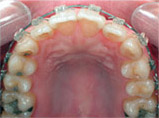

Before

Proceeding

After